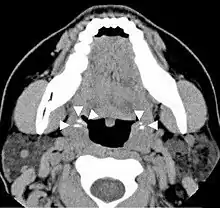

Occasionally there may be pain when swallowing.[7] Even when they are large, some tonsil stones are only discovered incidentally on X-rays or CAT scans. Other symptoms include a metallic taste, throat closing or tightening, coughing fits, and choking.

Diagnosis is usually made upon inspection. Tonsilloliths are difficult to diagnose in the absence of clear manifestations, and often constitute casual findings of routine radiological studies.

Imaging diagnostic techniques can identify a radiopaque mass that may be mistaken for foreign bodies, displaced teeth or calcified blood vessels. CT scan may reveal nonspecific calcified images in the tonsillar zone. The differential diagnosis must be established with acute and chronic tonsillitis, tonsillar hypertrophy, peritonsillar abscesses, foreign bodies, phlebolites, ectopic bone or cartilage, lymph nodes, granulomatous lesions or calcification of the stylohyoid ligament in the context of Eagle syndrome (elongated styloid process).[11]